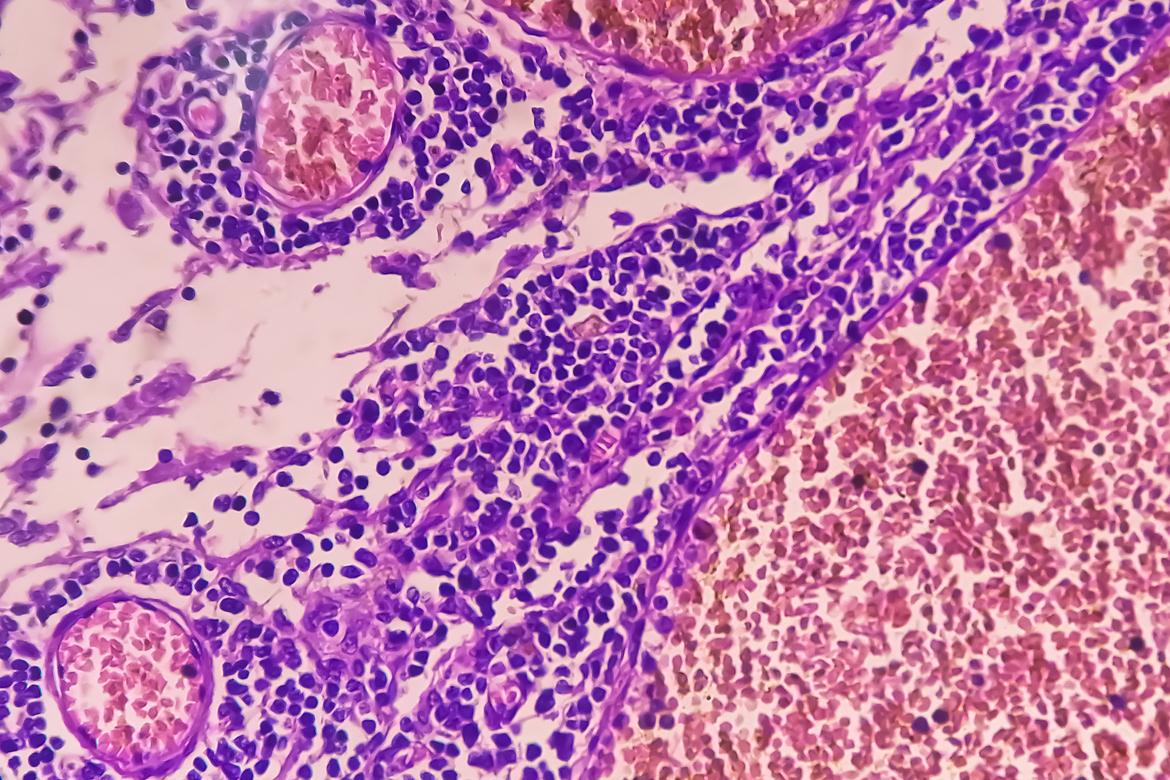

- Md Saiful Islam Khan/iStock